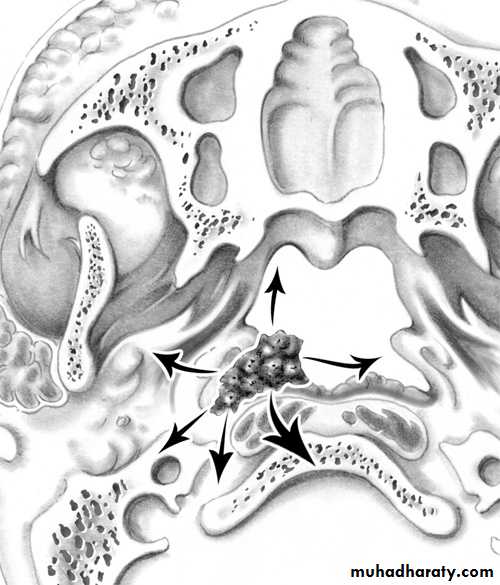

Most tumours arise from the fossa of Rosenmuller. In endemic areas undifferentiated carcinoma is the most common histological type.• Spread of Nasopharyngeal Carcinoma

• Direct, lymphatic (cervical L.N.) and blood borne (rare)

• -Anteriorly into the nasal cavity and paranasal sinuses leading to nasal symptoms.

• -Posteriorly to the retropharyngeal space and lymph nodes of Rouviere.

• -Laterally into the parapharyngeal space involving the last 4 cranial nerves.

• -Superiorly through the base of skull involving the optic nerve and the cavernous sinus.

• -Inferiorly to the oral cavity and retrotonsillar region.

Spread of NP Carcinomma